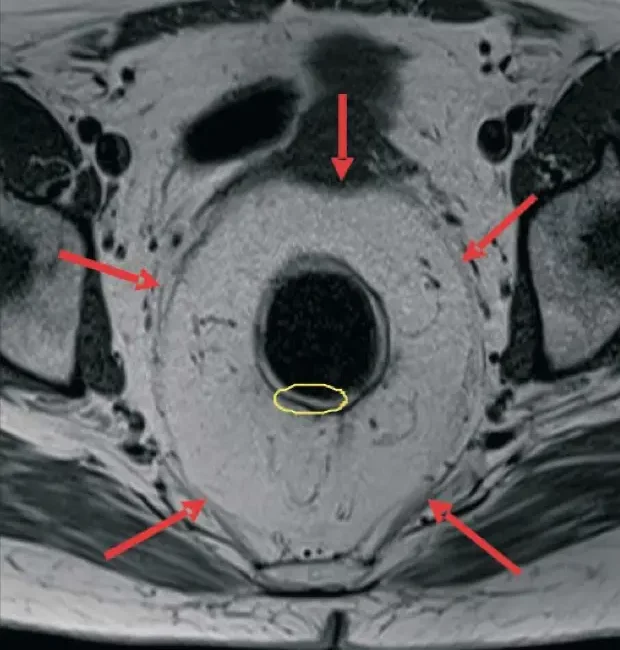

The preoperative imaging diagnosis of rectal cancer lies at the heart of oncological staging and has a crucial influence on patient management and therapy planning. Rectal cancer is common, and accurate preoperative staging of tumors using high-resolution magnetic resonance imaging (MRI) is a crucial part of modern multidisciplinary team management...

The reason a A) classic staging, B) modern staging or C) restaging is performed must be taken into consideration in order to have an appropriate staging. In general, staging is performed histopathologically after surgery, and offers information about the pTNM prognosis. The introduction of neoadjuvant therapy placed staging to the...

THE IMPORTANCE OF PREOPERATIVE STAGING OF RECTAL CANCER USING MULTIPARAMETRIC MRI. A SYSTEMATIC REVIEW – PART I

A correct preoperative stadialization of rectal carcinoma has a direct influence upon its therapeutic strategy, resulting in a significant improvement of the survival rate and life quality after the treatment. The therapeutic strategy refers to the option of undergoing or not preoperative radiochemotherapy before the total mesorectal excision (TME). The...